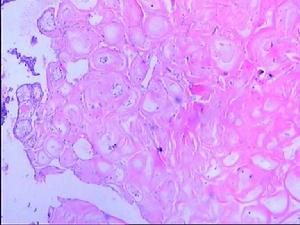

6.組織學檢查:本徵所發生的腸息肉在鏡下多數顯示為正常細胞的排列畸形或錯構瘤的結構。黏膜肌有帶有上皮成分的樹枝樣畸形,在息肉內有平滑肌纖維,上皮細胞雖然有異常排列,但亦為分化正常的杯狀細胞而無增生。